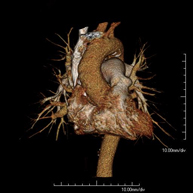

Prova diagnòstica que consisteix en l'estudi de l'aorta toràcica (principal artèria del tòrax) mitjançant l'ús d'un equip de TC (Tomografia Computeritzada). Aquesta tècnica requereix l'ús de contrast iodat i proporciona imatges d'alta definició. L'ús del TCMD (TC multidetector) escurça el temps d'exploració, disminueix la dosi de radiació i millora la qualitat d'imatge. Gràcies als múltiples detectors en determinats estudis es pot acoblar l'obtenció de la imatge amb el batec cardíac, tècnica que permet l'estudi de la vàlvula aòrtica i de l'arrel de l'artèria aorta (primers centímetres) on el batec del cor acostuma a provocar múltiples artefactes de moviment. - Angio –TC Artèries pulmonars (estudi TEP, Tromboembòlia pulmonar)

- Thoracic aorta CT angiography

Diagnostic test to examine the thoracic aorta (main artery of the thorax) using CT (Computed Tomography) equipment. This technique provides high-definition anatomical images. In most cases, the use of iodinated contrast is necessary. The use of MDCT (Multidetector Computed Tomography) shortens scanning time, reduces radiation dose and improves image quality. The multiple detectors used in certain studies enable imaging to be synchronised with the heartbeat, a technique used to study the aortic valve and aortic root (the first few centimetres), where the heartbeat tends to distort images due to movement.